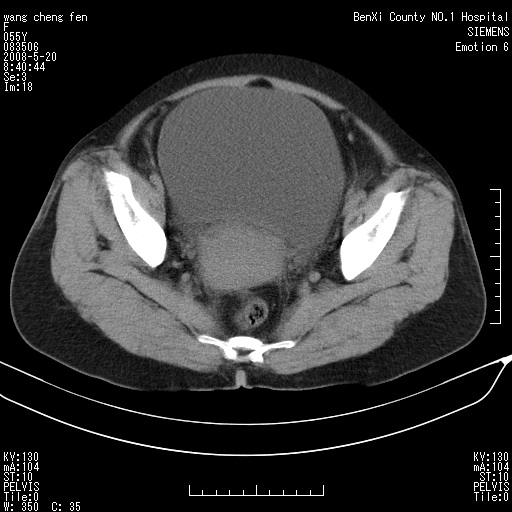

女、绝经后阴道流血3个月

宫颈好像也有问题吧,大家在仔细看看,另外彩超回报为卵巢占位。建议ct。

支持浆膜下子宫肌瘤.之前由于网络原因未看全图片,现在重看,宫颈见一类圆形低密度影,增强轻度强化,低于肌层强化,宫腔扩大,考虑宫颈癌伴宫腔积液可能性大.

1,宫颈部占位,宫颈癌?2,左侧附件区囊实性占位,界较清,实质部分强化明显。考虑浆膜下或阔韧带肌瘤囊变可能大。囊腺类肿瘤不除外。